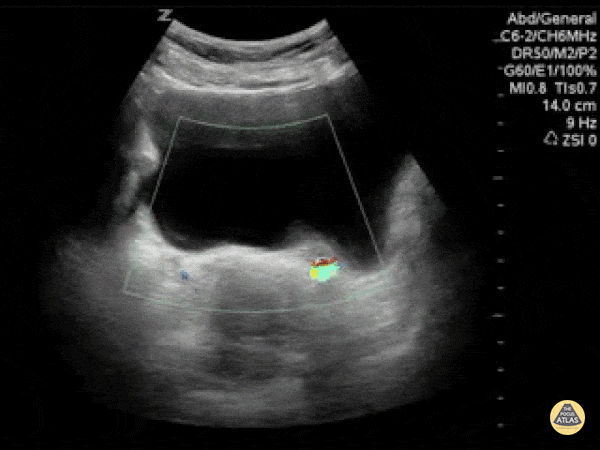

Renal/GU - Ureterovesical Junction Stone Twinkle Artifact

Twinkling artifacts can be seen on color doppler ultrasounds when applied to stationary, highly echogenic objects, generating a false sense of movement on color doppler. The reason this occurs is unclear. However, this is useful for kidney stones especially when they are in other echogenic environments such as the ureterovesicular junction. This scan demonstrates the twinkle artifact at the UVJ, thus a kidney stone that may have been missed otherwise. Dr. Justin Bowra et al. (Dr. Sutijono)